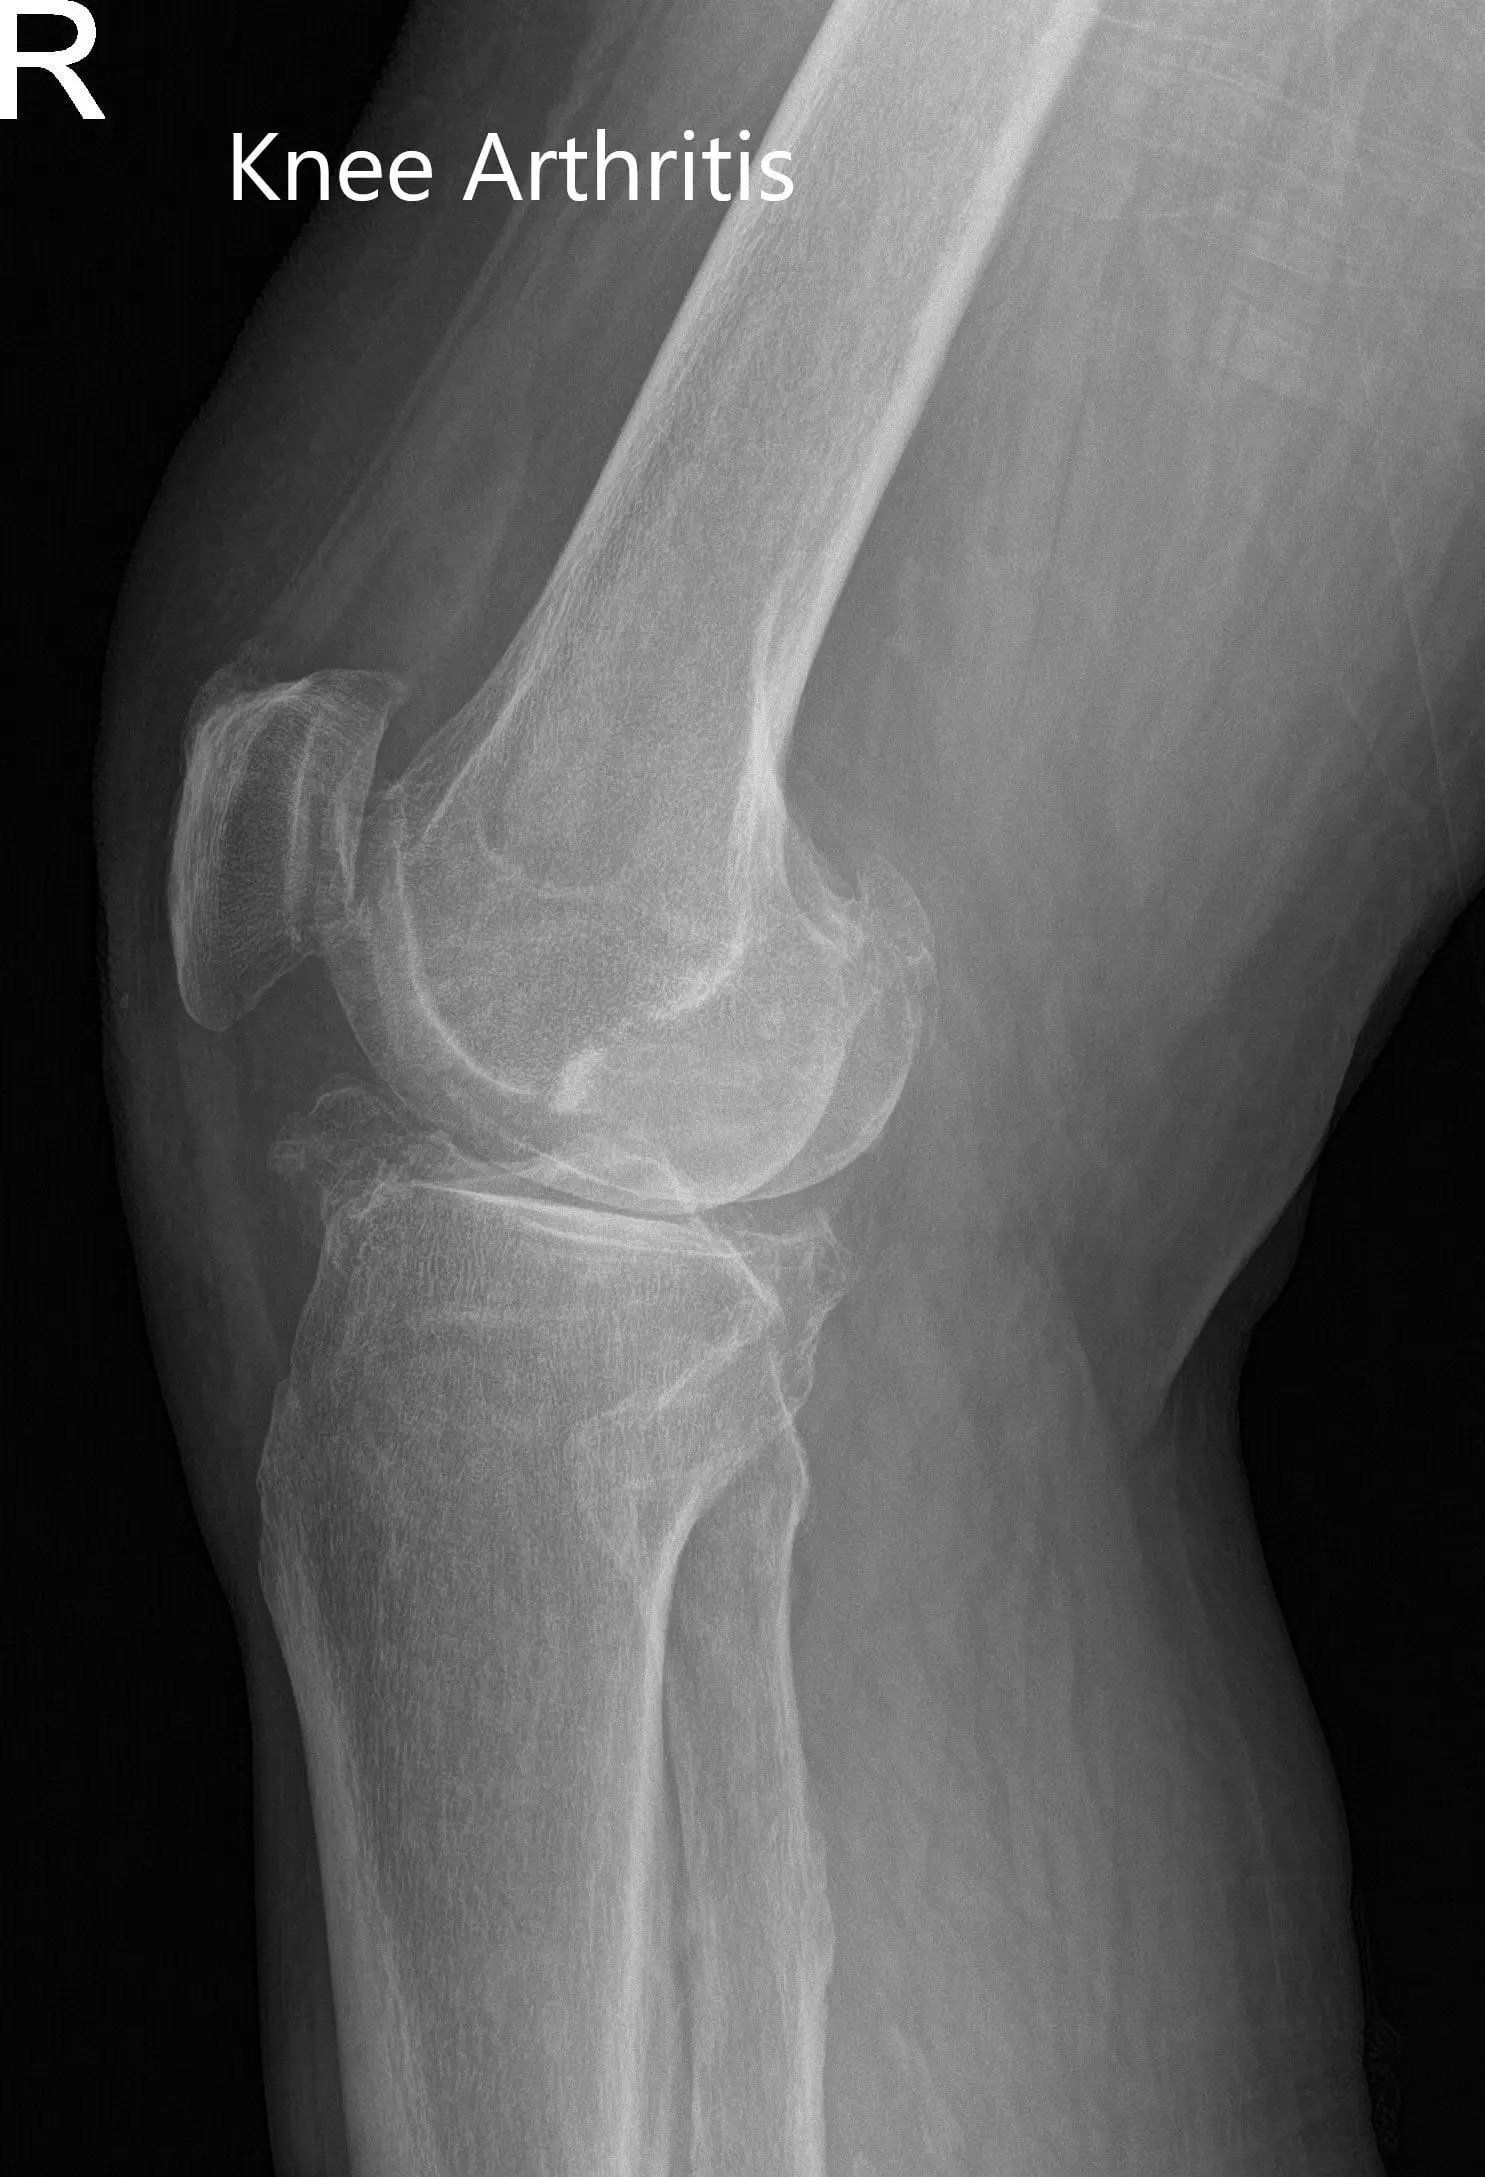

Imaging studies revealed severe bilateral knee arthritis. The right knee was worse than the left side. She was advised right total knee replacement with custom instruments. Risks, benefits, and alternatives were discussed at length with her. She agreed with the plan.

X-ray of the right knee in anteroposterior and lateral views.